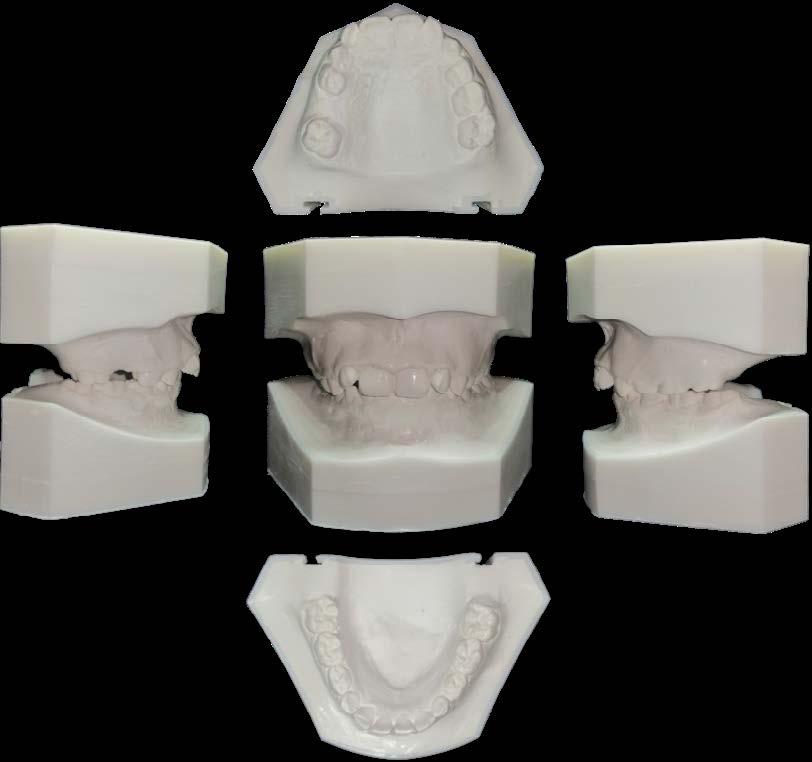

Es por lo anterior, que durante el intercambio dentario, la vigilancia periódica, a través de radiografías, análisis de modelos de estudio y una evaluación clínica, son acciones necesarias para la planeación adecuada de un tratamiento interceptivo, en caso de llegar a ser necesario, para generar los cambios y movimientos a nivel ortopédico y ortodóntico respectivamente y así evitar en lo posible una inclusión canina (Figura 7).

a. Observar radiográficamente las características anatómicas y dimensionales de los caninos superiores e inferiores respecto a dientes adyacentes (Figura 11).

b. Identificar radiográficamente la posición en que se encuentra el canino, respecto a los dientes adyacentes (Figura 12).

d. Conocer en qué estadio de Nolla está el desarrollo del canino (Figura 14).

f. Conocer el espacio necesario para el acomodo del canino en el arco dental.

g. Medir el espacio disponible en el arco dental para el acomodo del canino al momento del diagnóstico.

A partir de los 8 años, se puede observar radiográficamente el inicio de la reabsorción del canino deciduo (Figura 17).

El seguimiento del trayecto canino con un estudio radiográfico postero anterior, lateral de cráneo y ortopantomográfico, a partir de la edad señalada anteriormente, también es una herramienta efectiva que permite obtener un diagnóstico inicial, donde podrá observarse si se ha iniciado la reabsorción radicular del canino deciduo e identificar qué

dirección o trayecto está tomando el canino permanente (Figura 18).